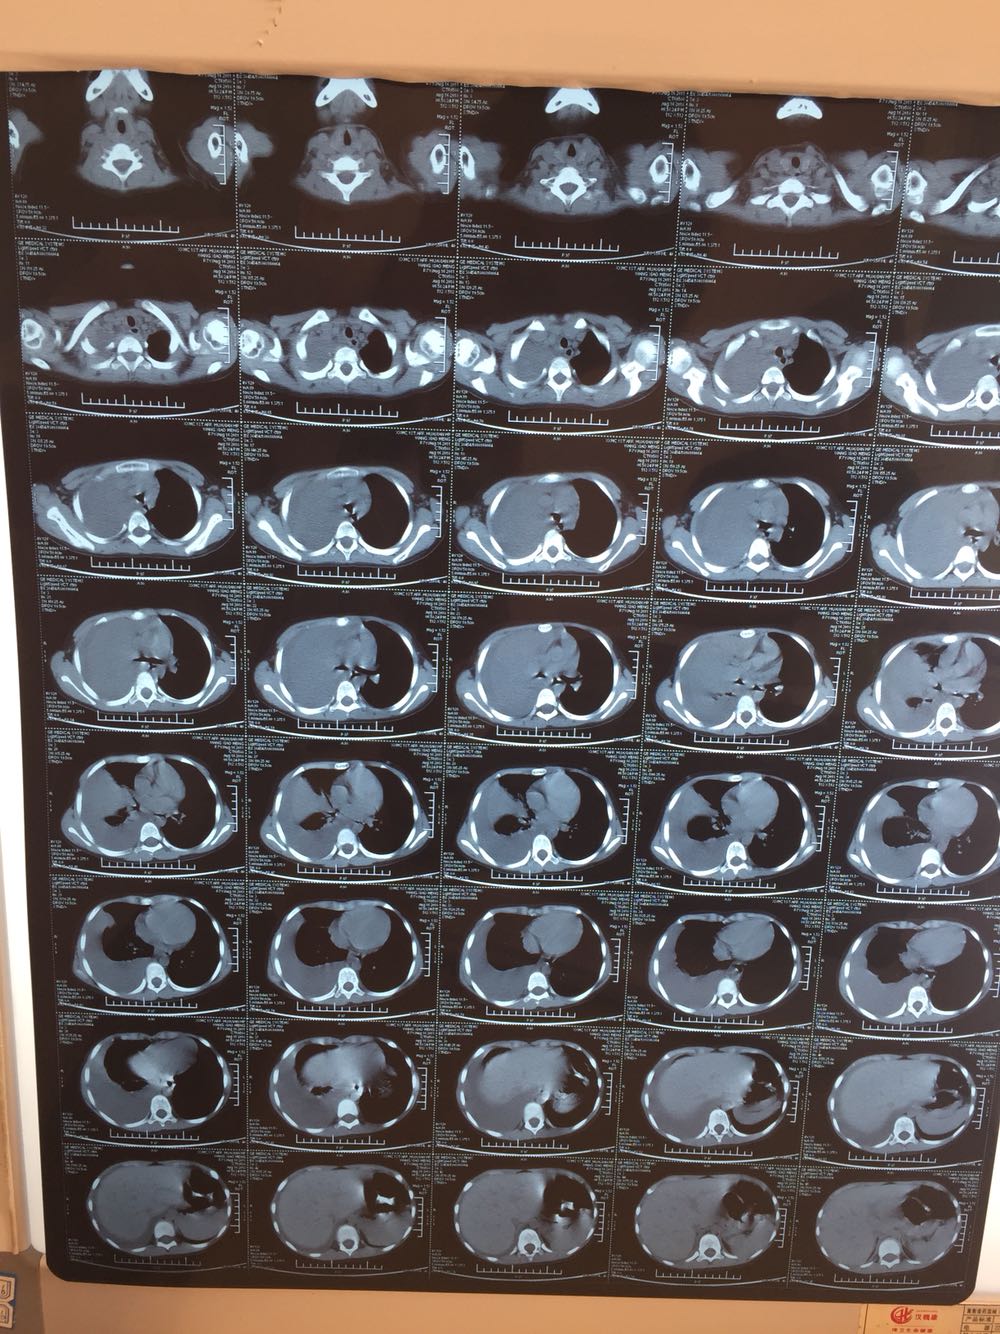

发热了,咳嗽7天,7天前患儿无明显诱因出现发热,咳嗽,体温最高39度,就诊于诊所,给予口服药物治疗,症状无好转

血常规白细胞8.3.中性粒细胞百分比65。CRP35mg/L

大叶性肺炎并肺不张并胸腔积液。脓毒血症,治疗上给予派拉西林联合阿奇霉素抗感染治疗

抗感染治疗一周后仍然反复发热,经科内会诊认为感染较重,发热是炎症感染所致,但家属要求转上级医院治疗